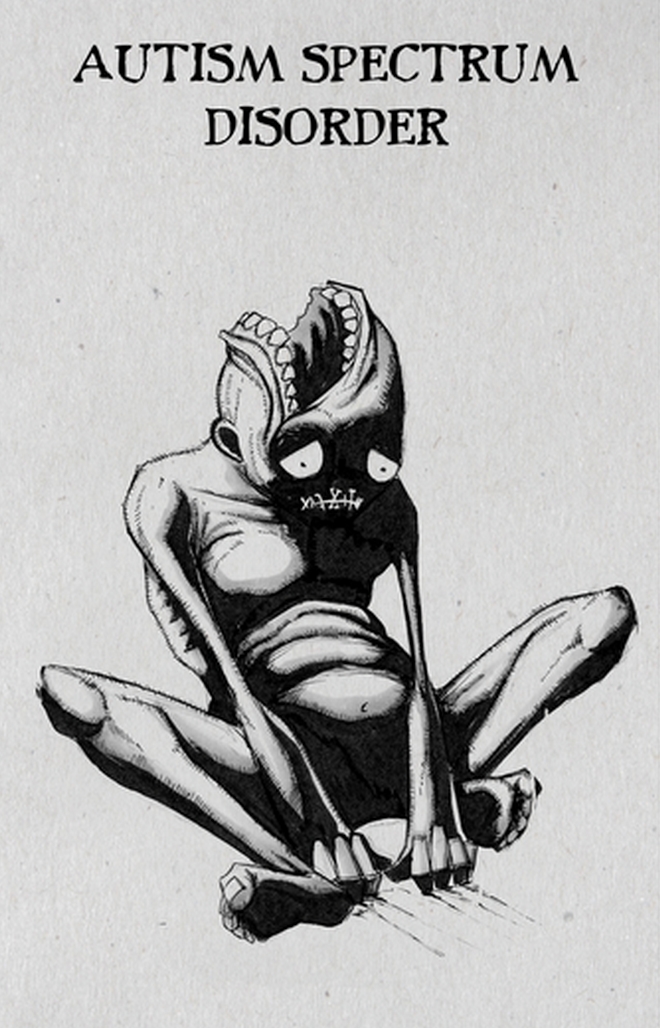

Αυτισμός

Δεν ξέρω αν ξεχωρίζω κάποιο αλλά υπάρχει μα ιστορία πίσω από το κομμάτι για τον αυτισμό, όπου απεικονίζω έναν νεαρό άνθρωπο που το στόμα του είναι στο πάνω μέρος του κεφαλιού του. Πολλοί μου επιτέθηκαν, λέγοντας ότι οι αυτιστικοί δεν είναι “τέρατα”, έτσι ερμήνευσαν την απεικόνισή μου. Τους απάντησα ότι στο σκίτσο δεν παρουσιάζω τον άνθρωπο ως τέρας αλλά το πώς βλέπει αυτός και οι άλλοι τη διαταραχή του. Χωρίς όμως να εννοώ ότι ένα αυτιστικό άτομο μπορεί να αποτελεί βάρος.

Θυμάμαι είχε έρθει μια κοπέλα σε ένα συνέδριο που ήμουν, η οποία έπασχε από αυτισμό, και μου είπε “έχω θέμα με τα σχέδιά σου”. Περάσαμε πάνω από μισή ώρα μιλώντας για το σκίτσο για να καταλάβουμε ο ένας πώς σκέφτεται ο άλλος. Αυτό θεωρώ είναι μια καλή αρχή.